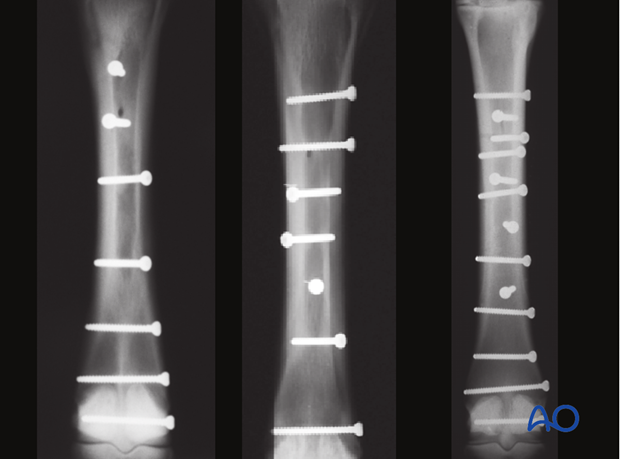

Removal of the diaphyseal and proximal metaphyseal screws is recommended if the horse is supposed to return to athletic function. Screw removal is generally performed about 3.5 - 4 months after surgery and is best done standing under sedation and local anesthesia. If general anesthesia is selected for some reason, use caution during the recovery process.